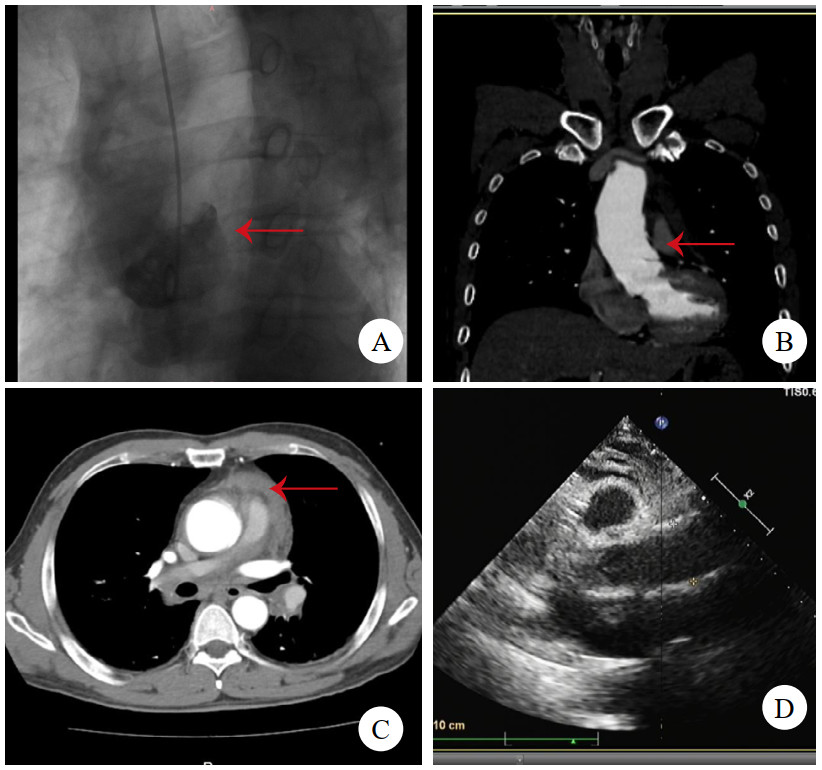

病例3,男,60岁,因“半小时前晕厥1次”就诊。送入抢救室时见患者大汗淋漓,显著呼吸困难,查体:心率97次/min,血压76/52 mmHg(1 mmHg=0.133 kPa),精神极软,颈静脉怒张,心音低钝,未及心脏杂音。立即查床边TTE,见大量心包积液(图 3A)。符合心包填塞,予心包穿刺,见血性液体流出约100 mL后,患者胸闷缓解,心率下降,血压138/88 mmHg。查主动脉CTA,见升弓交界靠上腔静脉侧LIT(图 3BCD),该处主动脉直径为31 mm,局部外膜薄层血肿形成。建议手术,患方拒绝,在抢救室留置6 h后生命体征突然消失,后宣布临床死亡。

注:A为TTE,箭头示大量心包积液伴血块;B为CTA横断面,箭头示内膜片;C为CTA冠状面,箭头示内膜片;D为CTA多平面重建,箭头示内膜片 图 3 例3患者TTE及CT影像